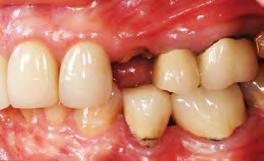

A healthy, 56-year-old female presented with fractured, endodontically treated tooth #9. The tooth was fractured at the gingival level and asymptomatic. Both the patient and the restorative dentist had high esthetic expectations, and preferred immediate implant placement with provisionalization if possible.

1. Pre-operative image showing a fractured, endodontically treated tooth #9.